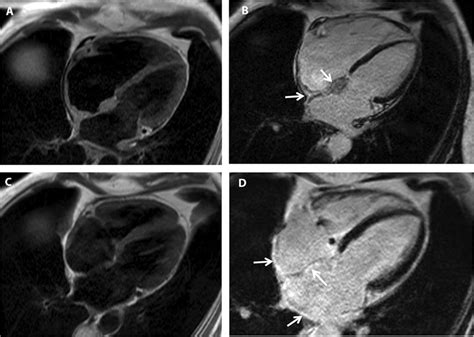

Cardiac MRI Identifies patterns of myocardial scarring and inflammation.